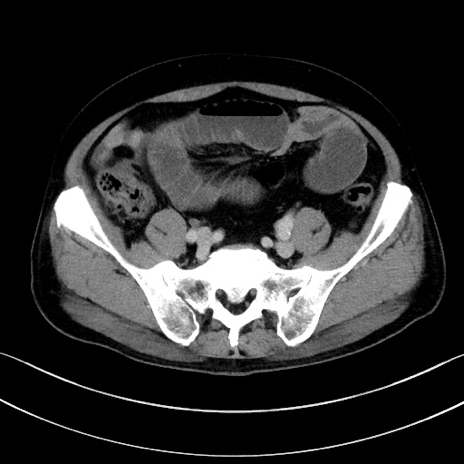

冠状断像

【症例】70歳代男性

【主訴】腹痛

【現病歴】今朝から腹痛あり。全体的に痛い。特に左上の方。排ガスが今日はない。冷や汗が出る。

【既往歴】直腸癌術後

【身体所見】左側腹部〜上腹部に圧痛あり。腹膜刺激症状明らかなではない。軽度反跳痛。左下腹部に術後瘢痕あり。

【データ】WBC 7700、CRP 0.02